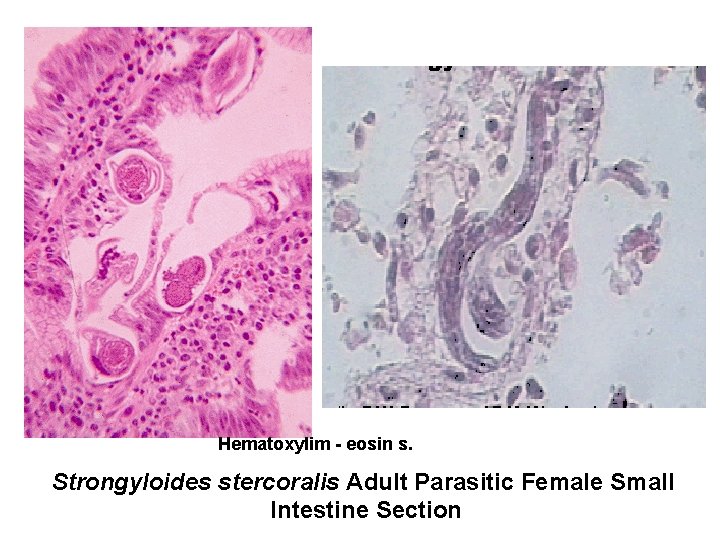

Hematoxylim - eosin s. Strongyloides stercoralis Adult Parasitic Female Small Intestine Section